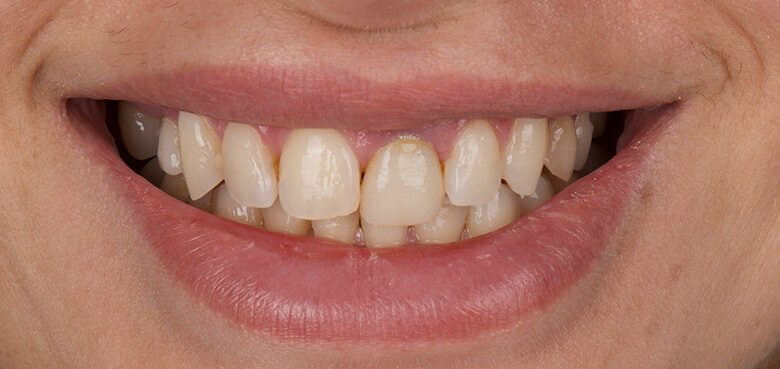

A 48-year-old male patient presented with a horizontal fracture of tooth #22 (Fig. 1). He complained of swelling of the tooth’s periapical area, and the periapical radiograph revealed a horizontal fracture with an unfavourable root–crown ratio (Fig. 2).

Fig. 1: Intra-oral pre-op situation of tooth #22, which had a horizontal fracture.